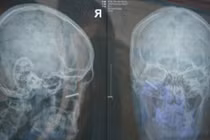

Sửa nhà đón Tết, nam thanh niên gặp tai nạn hy hữu

Anh N.V.H., 32 tuổi, trong quá trình sửa chữa nhà ở Long Mỹ - Hậu Giang, anh đóng đinh vào tường chẳng may cây đinh gãy một nữa và phần còn lại văng trúng mặt.

Những ngày Tết cận kề, một tai nạn hy hữu đã xảy ra mà sau khi phẫu thuật thành công các bác sĩ đã thở phào nhẹ nhõm “may quá!”.